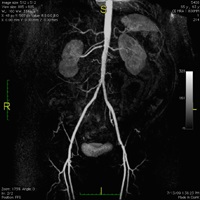

The figure at right is a contrast-enhanced image of Renal and Iliac arteries.